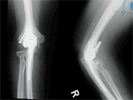

Post Op

X-Rays

X-rays elbow showing rheummatoid changes